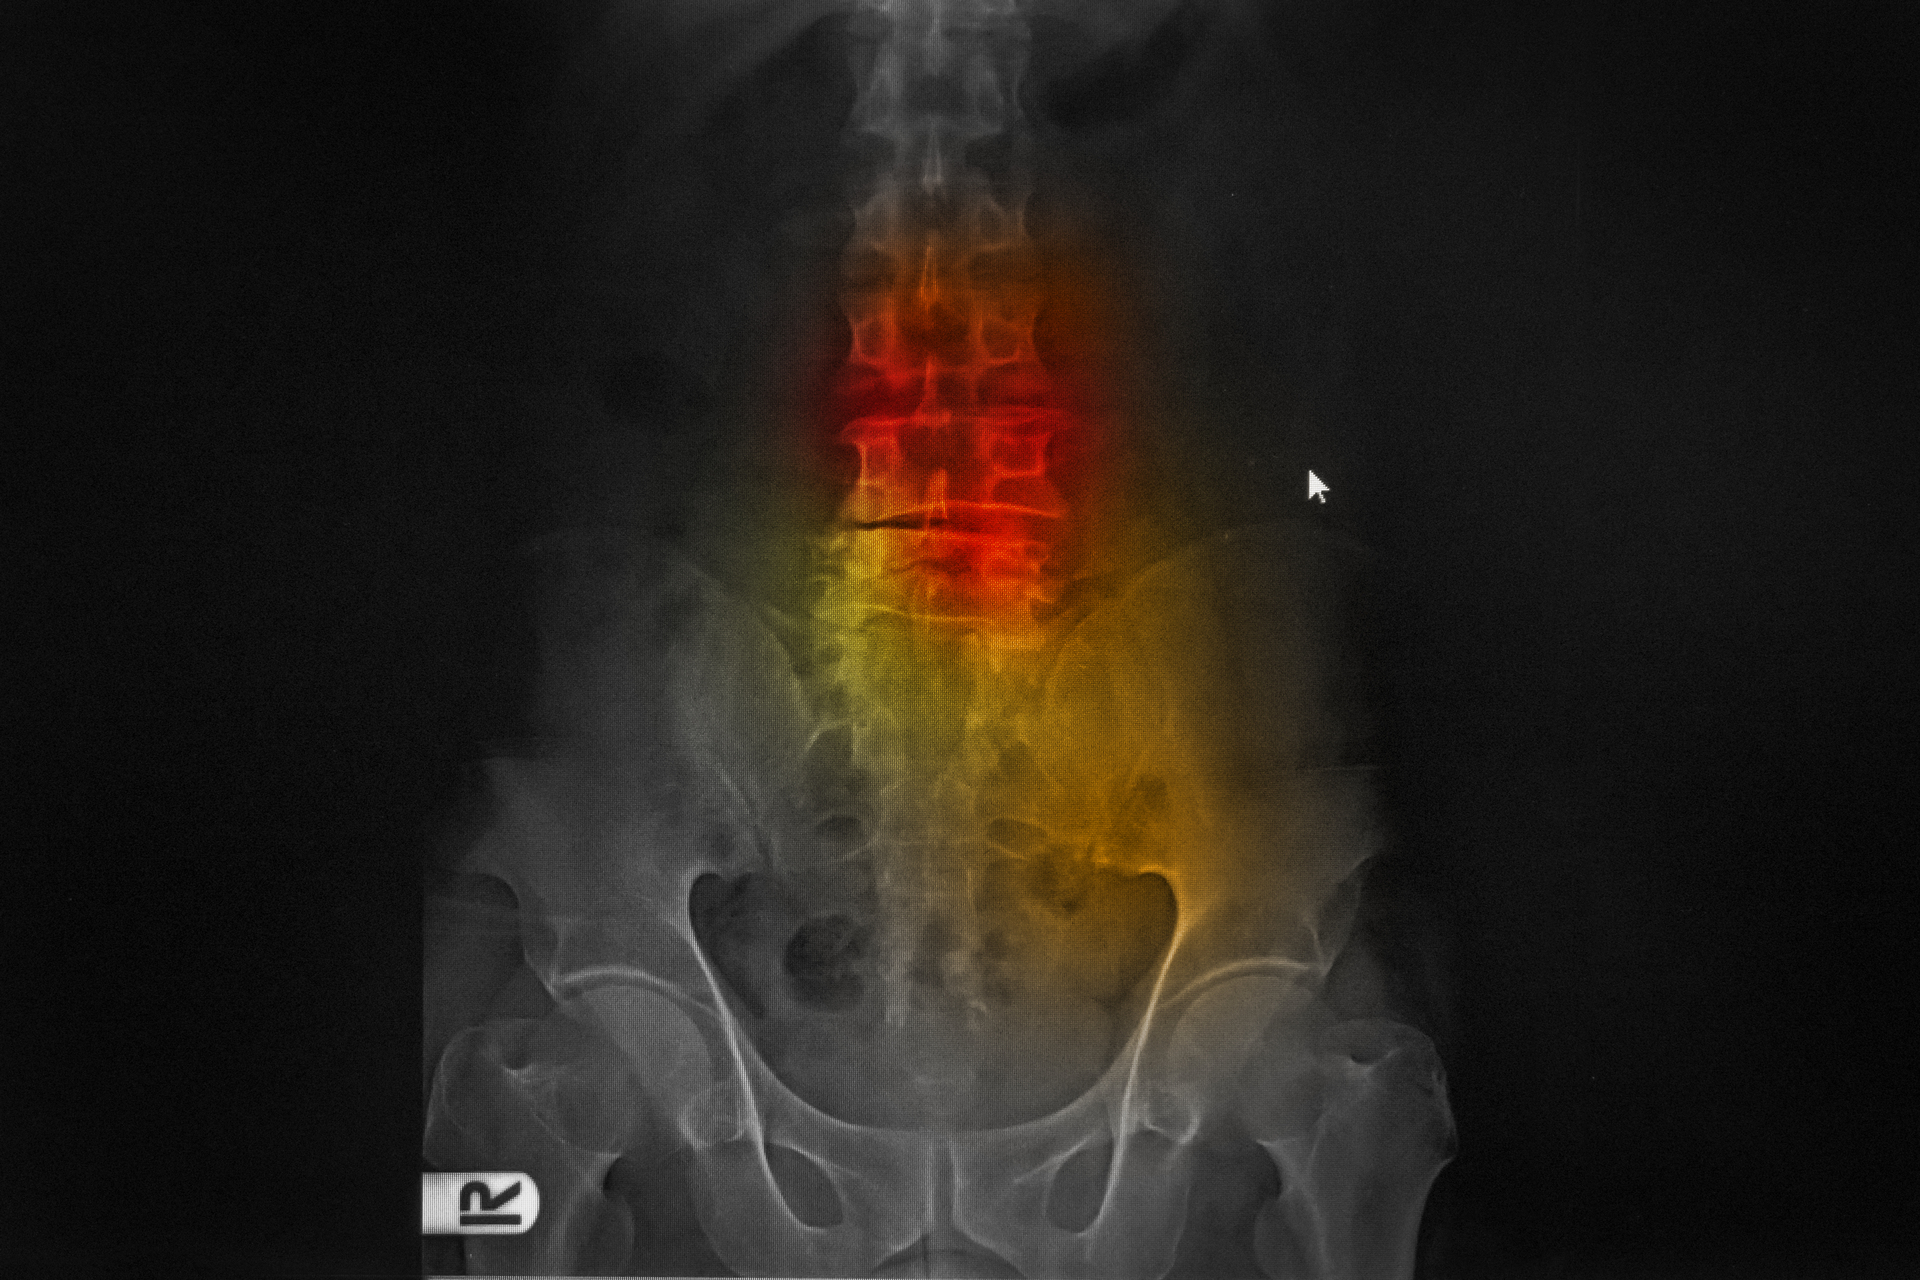

La región lumbar (columna baja) es la más comúnmente afectada, seguida de la cervical. Los discos torácicos (espalda media) rara vez se ven comprometidos. Puede acompañarse de sensaciones de hormigueo, entumecimiento o debilidad en el glúteo, el muslo, la pantorrilla o el pie. El dolor suele agravarse con maniobras que aumentan la presión en el disco, como toser, estornudar o hacer esfuerzo. Un signo de alarma que requiere atención médica inmediata es la pérdida de control de esfínteres (vejiga o intestino) o una debilidad muscular progresiva significativa, lo que podría indicar un compromiso severo de las raíces nerviosas. Para confirmar el diagnóstico, localizar con precisión la hernia y descartar otras patologías, se suele recurrir a estudios de imagen. La resonancia magnética es la prueba de elección, ya que muestra con claridad los tejidos blandos, los discos, los nervios y el grado de compresión. Una tomografía computarizada puede ser una alternativa.